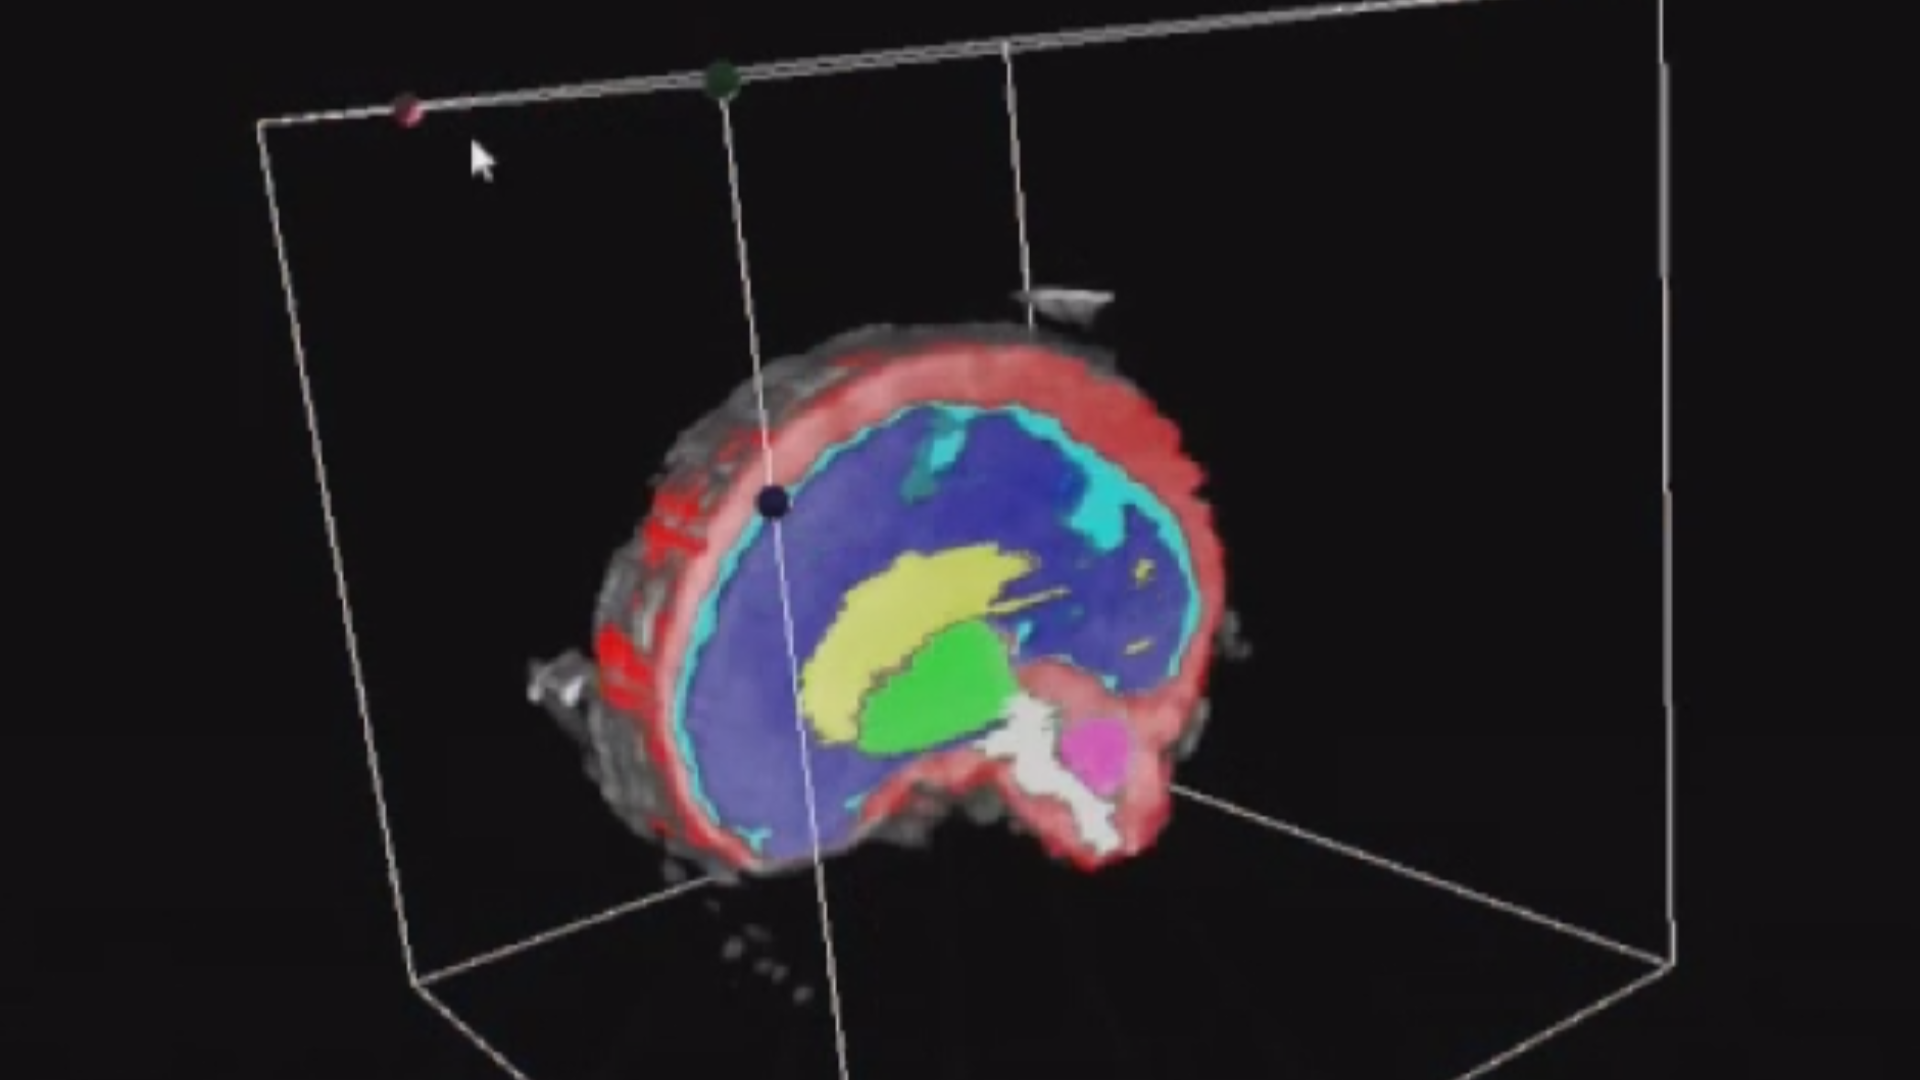

L’Université Paris Cité franchit une nouvelle étape dans le domaine de l’imagerie médicale anténatale avec l’acquisition d’un système d’Imagerie par Résonance Magnétique (IRM) 1,5T ARTIST™ de GE HealthCare. Cet équipement de pointe renforce les capacités de la Plateforme LUMIERE à l’hôpital Necker-Enfants malades, plateforme intégrée de soins, de recherche clinique et d’enseignement en imagerie médicale de la femme enceinte, du fœtus et du placenta.

Une avancée technologique majeure pour la recherche anténatale

L’acquisition de cette nouvelle IRM s’inscrit dans le cadre du protocole de recherche « LUMIERE SUR LE FETUS », dont les objectifs sont d’améliorer la prise en charge des pathologies anténatales, d’affiner leur pronostic et de contribuer à la réduction de la morbidité et de la mortalité à court, moyen et long terme. Cette acquisition a été rendue possible grâce au don exceptionnel de la Fondation LUMIERE d’un montant de 250k euros ainsi qu’au soutien de l’Université Paris Cité à hauteur de 670k euros.

Implantée à l’hôpital Necker-Enfants malades, la Plateforme LUMIERE est une plateforme unique au monde, qui a vu le jour grâce notamment au soutien de l’Université Paris Cité, de l’AP-HP et de la Fondation LUMIERE.

Une plateforme au service de la recherche et des patientes enceintes

L’inclusion de ces patientes, depuis leur accueil jusqu’à la réalisation des examens d’imagerie, puis l’analyse des images et l’interprétation des résultats par des équipes expertes, enrichit une base de données structurée, unique au monde, au service de la recherche et de l’innovation en imagerie anténatale et en médecine fœtale.